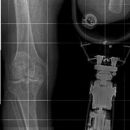

Ganzbeinaufnahme mit Beinprothese